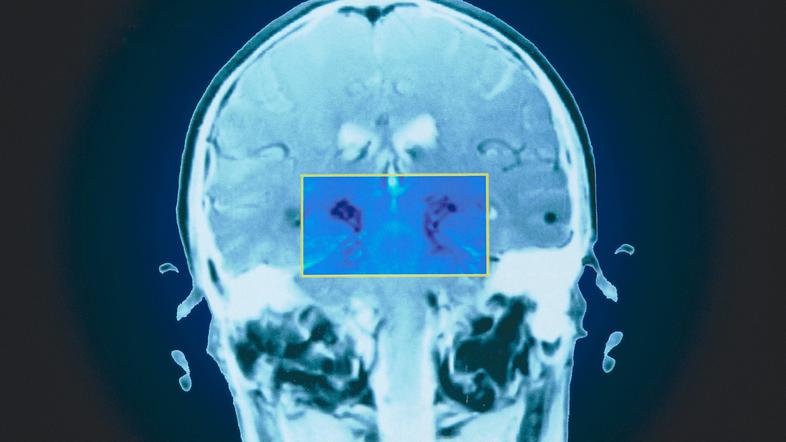

Parkinsonova bolezen nastane zaradi motnje v omrežju nigrostriatnih dopaminergičnih nevronov. | Avtor: Profimedia Profimedia